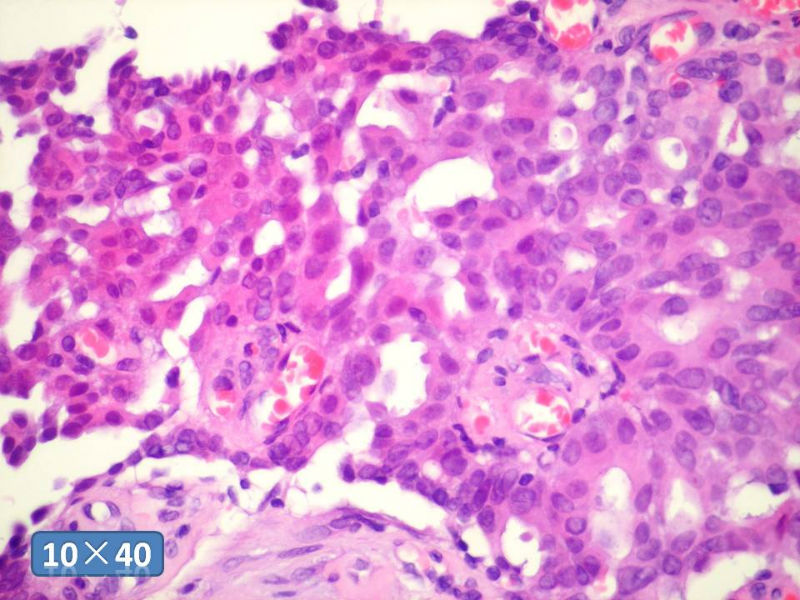

只能说是乳头状瘤

是不是导管内

乳头状瘤 and 导管内乳头状瘤 are the same; Benign lesion.

After you work up and you still cannot be sure it is benign , atypical or maignant lesion, you can call 乳头状lesion.

If this is excisonal case, you should figure out the nature of the papillary lesion.

我的意思就是提醒大家 在不是很确定的情况下 尽量少给自己套枷锁